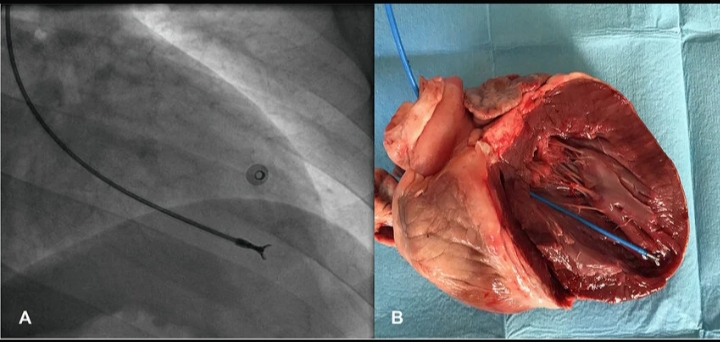

The procedure is typically performed using a thin catheter inserted through a vein in the neck or groin and guided into the heart. A small device attached to the catheter collects tissue samples from the inner lining of the heart.

Guidance to the heart – Imaging techniques such as fluoroscopy are used to guide the catheter into the heart.

Collection of tissue samples – Small fragments of heart muscle are removed using specialized instruments.